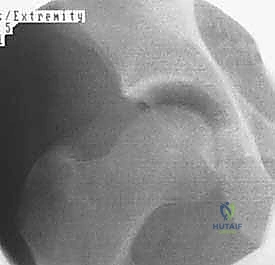

منظار الورك هو إجراء جراحي طفيف التوغل (Minimally Invasive) يتيح للجراح رؤية داخل مفصل الورك دون الحاجة إلى عمل شق جراحي كبير. يتم ذلك من خلال إدخال كاميرا دقيقة جداً (Arthroscope) متصلة بشاشة عرض عالية الدقة (4K) عبر شقوق صغيرة لا تتجاوز نصف سنتيمتر في الجلد.

من خلال هذه الرؤية المكبرة والواضحة، يستطيع الأستاذ الدكتور محمد هطيف فحص وتشخيص الأضرار بدقة متناهية، ثم إدخال أدوات جراحية دقيقة عبر شقوق أخرى صغيرة لإصلاح التمزقات، أو إزالة الشظايا العظمية، أو تقليم الغضاريف التالفة.

3. تقييم الضرر والإصلاح

بناءً على التشخيص المسبق والرؤية المباشرة، يبدأ الجراح في العمل:

* إذا كان هناك تمزق في الشفا، يتم استخدام أجهزة خياطة دقيقة لتثبيته.

* إذا كان هناك اصطدام عظمي (FAI)، يتم استخدام جهاز حفر ميكروسكوبي (Shaver/Burr) لنحت العظم الزائد وإعادة تشكيله.